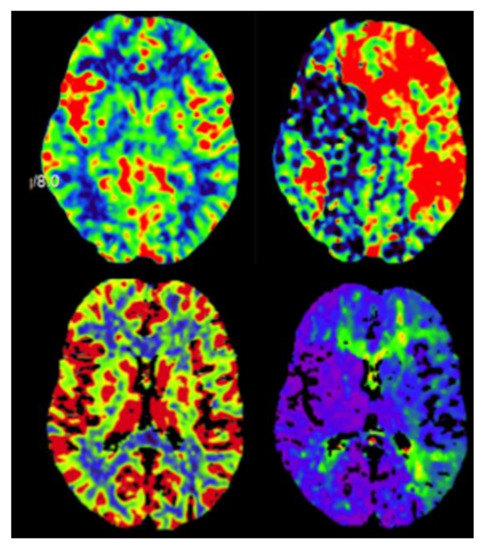

2. Case Description